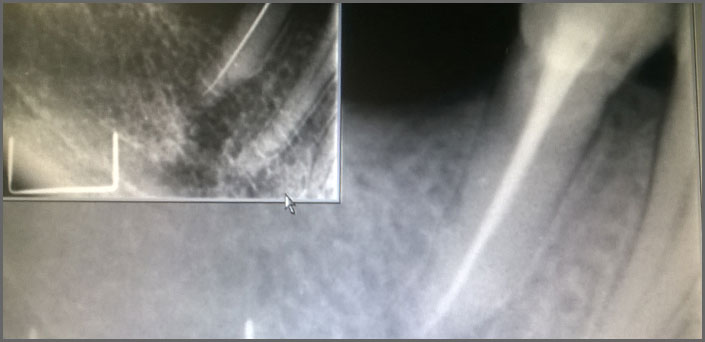

Σας παρουσιάζουμε κάποια ενδιαφέροντα στοματολογικά περιστατικά που διαγνώσαμε στο ιατρείο μας: